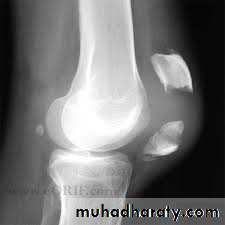

Knee joint (anatomical view)Dislocation of the patella

Because the knee is normally angled in slight valgus, there is a natural tendency for the patella to pull towards the lateral side when the quadriceps muscle contractd laterally by violence.Mechanism of injury :

sudden, severe contraction of the quadriceps muscle while the knee is stretched in valgus and external rotation.

Patients with joint hypermobility, valgus knee, muscle and joint abnormalities prone to this injury.

Clinically :

The knee collapses and patient fall on ground.

Patella can be felt on outer side of knee or the patella springs back into position spontaneously.

The X- ray

shows dislocation of patella laterally and associated fractures if present.